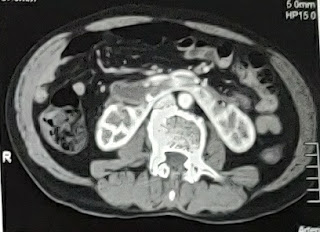

70 year old male with right sided flank pain

Renal Caliculi In Right Kidney which is 20mm in size

Radioimaging:

USG report:

Doppler: